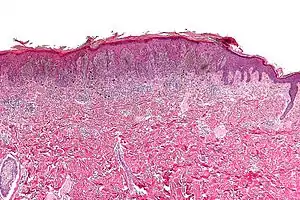

| Micrograph of a pigmented spindle cell nevus (top of image). H&E stain. | |